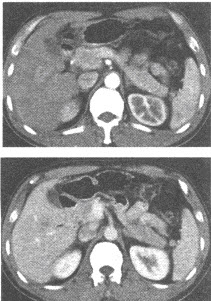

男,41岁。HBsAg(+),AFP45μg/ml。体检超声发现肝右叶有26mm×23mm大小低回声结节。CT增强扫描如图所示。最有可能的诊断为()

A:肝血管瘤

B:肝细胞癌

C:肝炎性假瘤

D:脂肪肝

E:肝腺瘤